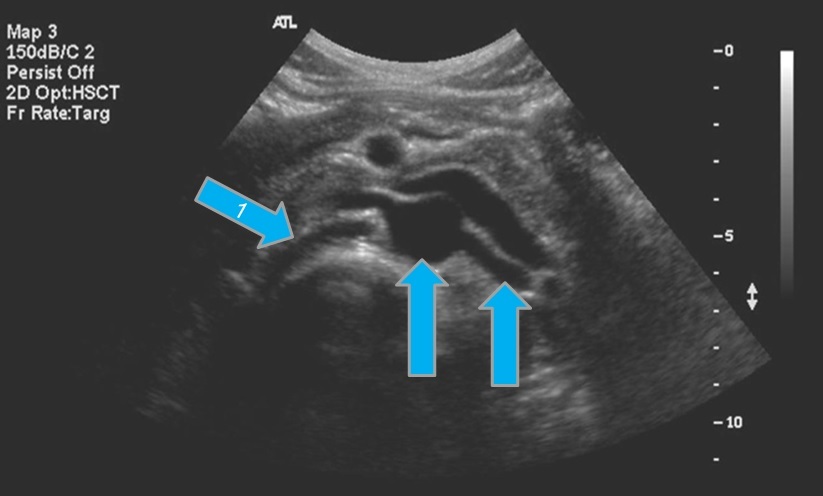

4

From the left to right label the structures

A

1. Gastroduodenal artery this is in the head of the pancreas

2. Porta of confluence

3. Splenic vein